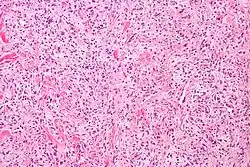

| Micrograph of a solitary fibrous tumor. H&E stain. | |